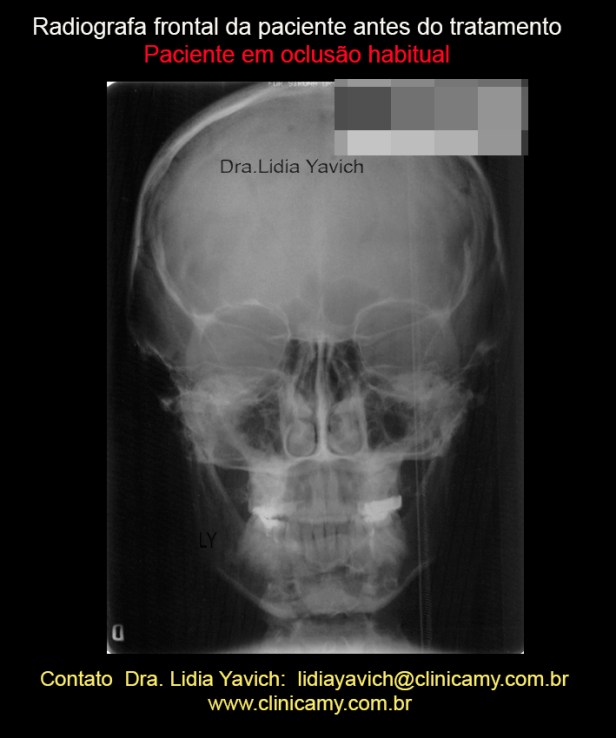

Radiografia frontal da paciente em oclusão habitual antes do tratamento.